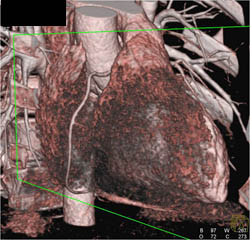

Plaque in LAD